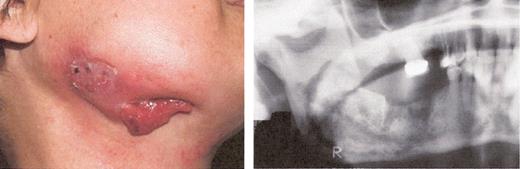

Stage I osteonecrosis of the jaw (ONJ). Patient with myeloma on zoledronic acid for 18 months.

Stage II osteonecrosis of the jaw (ONJ). Patient on zoledronic acid for 18 months.

Stage III osteonecrosis of the jaw (ONJ). Patient on pamidronate for 54 months followed by zoledronate for 18 months.